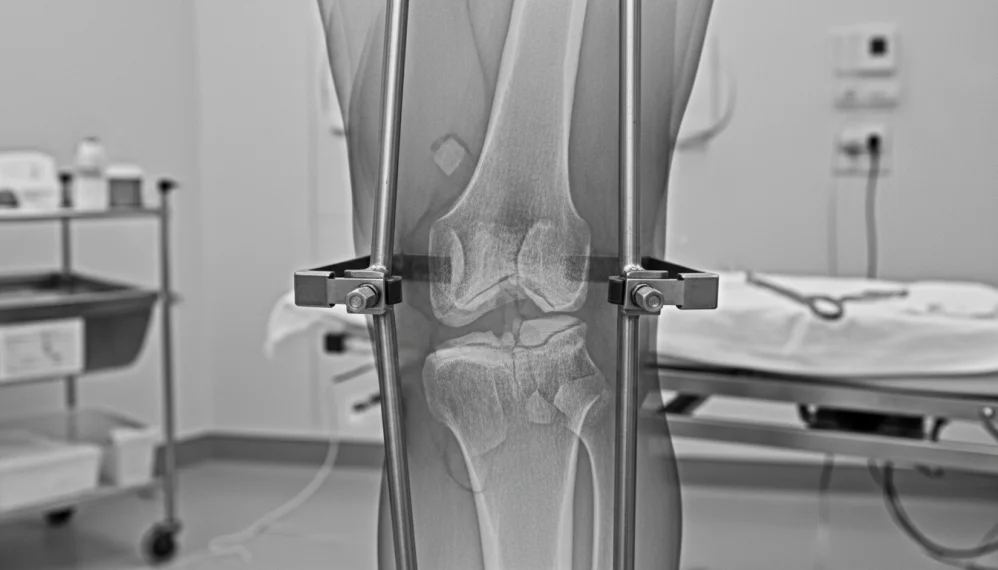

Diagnostic

Este destul de usor de sustinut pe baza semnelor clinice. Radiografia este obligatorie pentru descrierea tipului de fractura, cu sau fara deplasare (mai frecventa la copii), precum si precizarea directiei si formei traiectului de fractura (simpla sau cominutiva) si a deplasarii fragmentelor. Radiografia executata din doua pozitii (fata si profil), cuprinde obligatoriu articulatia gleznei si genunchiului.